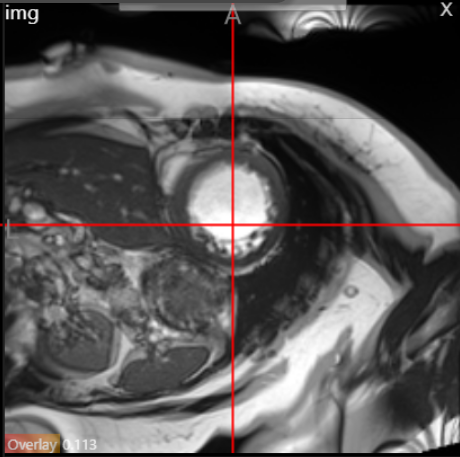

To provide a qualitative evaluation, Figure 3 illustrates a sample MRI slice from the ACDC dataset, along with the corresponding prediction and ground truth segmentation masks generated by our CFPFormer model. The figure demonstrates the model’s ability to accurately segment intricate anatomical structures, such as the left and right ventricles, and the myocardium.

Refer to caption

(a) Input Image

(b) Prediction

(c) Ground Truth

Figure 3: ACDC segmentation example: (a) Original MRI slice, (b) Prediction result of CFPFormer, and (c) Ground truth segmentation masks.